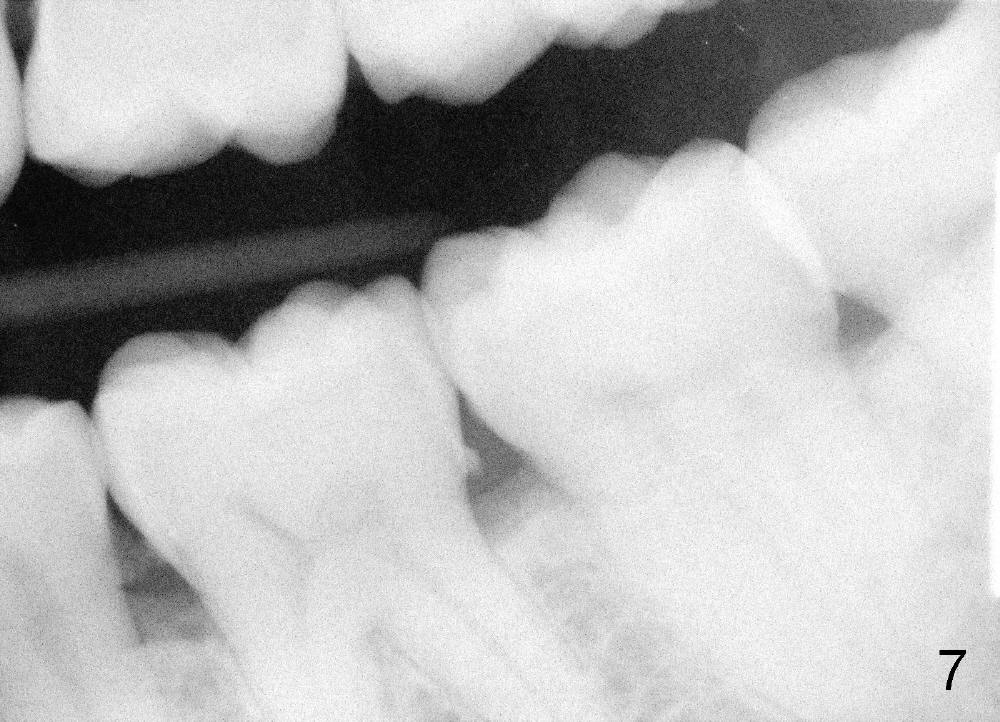

Forty-year-old man had ortho with extraction in his teens (Fig.1,2: B: bicuspid). Without wearing retainers, relapse occurs, particularly in the lower anterior. The lower left central incisor shifts labially with gingival recession (Fig.2,3). The attached gingiva is narrow for this incisor as compared to that of the neighboring tooth (Fig.4 between arrowheads). Although there is abundance of calculus, bone loss is mild to moderate (Fig.5-7). Scaling and root planing was finished today with schedule of perio maintenance every 3 months.